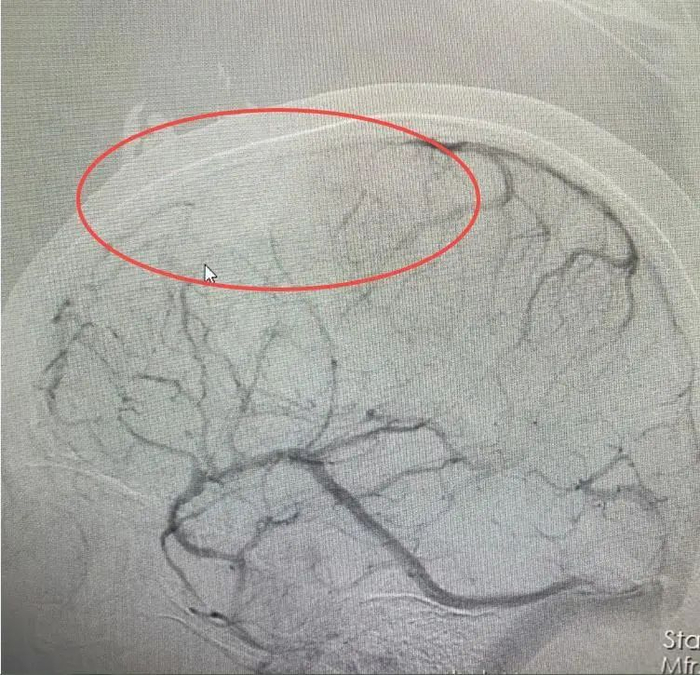

医院接诊医生仔细分析后,发现婷婷颅内病变不是脑肿瘤。结合病史和相关影像资料,该院神经内一科副主任匡祖颖初步怀疑是颅内静脉窦血栓。进一步完善全脑血管造影,证实是颅内静脉窦血栓形成合并出血。

据了解,颅内静脉窦血栓与血管病变、血液成分改变以及不良生活习惯和过度疲劳等有关。神经内科专家解析:“患者原本就贫血,不科学的减肥方法加重了贫血,加之长期熬夜,饮食、作息极不规律,导致血液处于高凝状态,这是静脉窦血栓形成的主要因素。”